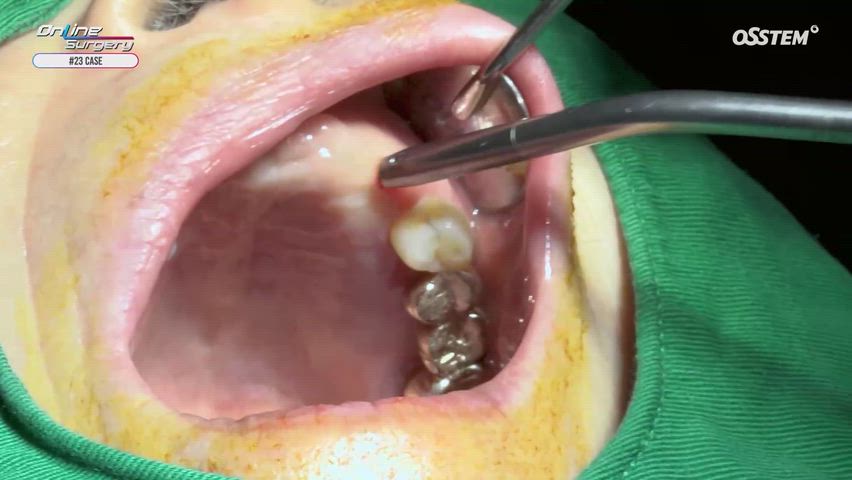

#35i, #37i 2nd surgery & Free Gingival Graft

Online Surgery

Views 13